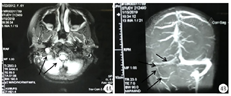

实验室和辅助检查:血常规:白细胞计数(white blood cell count,WBC) 5.06×109/L,中性粒细胞百分比(neutrophils%,N% )40.9 %,红细胞计数(red blood cell count,RBC) 4.22×1012/L,血红蛋白(hemoglobin,Hb)115 g/L,血小板计数(platelet count,PLT) 202×109/L。尿、粪常规正常。血生化大致正常。血清乳酸脱氢酶(lactate dehydrogenase,LDH)859 U/L。C反应蛋白(C reactive protein,CRP)112.7 mg/L。红细胞沉降率(erythrocyte sedimentation rata,ESR)94 mm/h。降钙素原(procalcitonin,PCT)0.51 μg/L。凝血:国际标准化比值(international normalized ratio,INR)1.21,活化部分凝血活酶时间(activated partial thromboplastin time,APTT)26.60 s。D-二聚体11.10 mg/L。肺炎支原体抗体IgM 1 527 U/ml。肺炎支原体RNA阳性。副流感病毒1、2和3型抗体IgM阳性。甲流抗体IgM阳性。结核抗体、结核感染T细胞检测、结核菌素试验、EB病毒系列、EB病毒DNA、沙眼衣原体抗体、双份血培养均正常。胸部CT示右肺下叶可见斑片状高密度影,边缘模糊,考虑大叶性肺炎(图1)。心脏B超未见明显异常。双下肢血管彩超示右侧下肢动脉改变,考虑闭塞性动脉炎可能。

入院治疗:给予一级护理,血氧心电监护,测血压(右侧腘窝血压测不出),嘱卧床,抬高右下肢,局部保暖,给予美罗培南抗感染,阿司匹林肠溶片(国药准字:H13021127,石药集团中诺药业有限公司),25 mg/次,口服,1次/d、低分子肝素钙(国药准字:H20010300,海南通用同盟药业有限公司),100 IU/kg,肌肉注射,每12小时1次、前列地尔(国药准字:H20103101,西安力邦制药有限公司),1 ml,静脉注射,1次/d,抗凝改善循环,帕拉米韦(国药准字:H20130029,广州南新制药有限公司)抗病毒等治疗。入院第2天,患儿仍有反复发热,查体双眼结膜充血,换予美罗培南(国药准字:J20140170,Sumitomo Dainippon Pharma Co Ltd)联合替考拉宁(国药准字:H20093651,浙江海正药业股份有限公司)抗感染治疗,同时予静脉注射人免疫球蛋白(国药准字:S10970032,华兰生药工程股份有限公司),2 g/kg支持治疗。入院第3天患儿仍有反复发热,完善支气管镜检查及肺泡灌洗术,可见各支开口黏膜粗糙,少量稀白分泌物附着,右肺下叶分泌物较多,局部灌洗右肺下叶后可见较多稀白分泌物,管壁毛糙(图2A、图2B)。查下肢血管B超示右侧髂总动脉,髂内动脉起始段、髂外动脉、股总动脉、股浅动脉近心段、股深动脉起始段、腘动脉、胫前动脉、胫后动脉内径、肌间动脉、足背动脉管壁僵硬,管腔内均可见暗淡回声充填,血流信号缺失。全腹部CT示右髂血管密度增高,考虑闭塞性动脉炎。予全身麻醉下行股动脉切开取栓术,分别于股动脉远端、股动脉近端、股深动脉远近端取出长度分别为5.0、4.0、0.5、0.5 cm的血栓(图2C)。入院第4天,患儿体温逐渐正常,右下肢疼痛好转,查体:右小腿中远端及足部皮温暖,可触及明显足背动脉搏动,右足趾甲红润,充血试验正常,复查双下肢血管B超右侧动脉取栓术后,右侧髂总动脉内中膜略厚,回声稍强,右侧股浅、腘、胫前动脉峰值流速较对侧略低,余未见异常。入院第6天,患儿再次出现发热,头痛,具体性质不详,可耐受,伴嗜睡,仍有咳嗽咳痰,复查D-二聚体8.79 mg/L,血清铁蛋白708.25 μg/L,ESR 41 mm/h;复查胸部CT示大叶性肺炎并大量胸腔积液,胸部B超示双侧胸腔积液(右侧大量,左侧少量),胸腔积液常规、生化、染色、培养未见明显异常。肺泡灌洗液培养示革兰阳性球菌,400 cfu/ml。头颅MRI示右侧乙状窦显影浅淡,MRV颈内静脉未见明确显示,考虑血栓可能,脑实质未见异常(图3A、图3B)。脑脊液常规、生化、染色、培养未见异常。换予亚胺培南西司他丁(国药准字:H20084018,珠海联邦制药股份有限公司)联合阿奇霉素(国药准字:H2000426,东北制药集团沈阳第一制药有限公司)序贯治疗,抗感染,布地奈德(国药准字:H20140474,AstraZeneca Pty Ltd)、异丙托溴铵(国药准字:H20150173,SCS Boehringer Ingelheim Comm.V)联合沙丁胺醇(国药准字:H20160660,GlaxoSmithKline Australia Pty Ltd.)雾化止咳化痰,前列地尔抗凝,贝前列素钠(国药准字:H20083589,北京泰德制药股份有限公司)抗血小板,醋酸泼尼松片(国药准字:H33021207,浙江仙琚制药股份有限公司),10 mg/次,口服,3次/d抗炎,合并中药综合治疗。入院第13天,患儿体温正常,精神好转,咳嗽咳痰较前减轻,复查D-二聚体13.11 mg/L,凝血:纤维蛋白原5.73 g/L,加低分子肝素钙抗凝。入院第21天,复查胸部B超示未见胸腔积液,予醋酸泼尼松片逐渐减量至停药。共住院22 d,病情平稳出院。

入院后给予一级护理,低流量鼻导管吸氧,亚胺培南西司他丁联合红霉素(大连美罗大药厂,国药准字:H21021678)抗感染,盐酸氨溴索(Boehringer Ingelheim Pharma GmbH & Co.KG,国药准字:J20140032)化痰,布地奈德、异丙托溴铵联合沙丁胺醇雾化止咳化痰,甲泼尼龙琥珀酸钠(国药准字:H20170197,甲泼尼龙琥珀酸钠)抗炎,多烯磷脂酰胆碱(成都天台山制药有限公司,国药准字:H20057684)保肝,更昔洛韦(湖北科盖药业股份有限公司,国药准字:H10981089)抗病毒治疗。入院第7天患儿体温正常,咳嗽咳痰减轻,精神仍稍差,偶有头痛,具体性质不详,可耐受。复查血常规:WBC 14.21×10 9/L,N% 70.2%,RBC 3.93×1012/L,Hb 11 g/L,PLT 360×109/L。尿常规正常。CRP 0.81 mg/L。ESR 63 mm/h。复查胸部CT示肺炎病灶较前吸收不明显,胸部B超示左侧胸腔积液(微量),完善支气管镜及肺泡灌洗术,镜检可见左肺各支开口黏膜粗糙,少量稀白分泌物附着,右肺开口处黏膜粗糙,红肿,右肺中叶分泌物较多,局部灌洗右肺中下叶后可见较多稀白分泌物。肺泡灌洗液培养示革兰阳性球菌,偶见,白细胞(+++)。脑脊液细胞学常规、生化、染色、培养均正常。头颅CT示右侧横窦走行区局部密度增高,大脑脑沟增宽。头颅MRI/MRV/MRA示右侧颈内静脉、乙状窦及横窦走行区信号增高,MRV示右侧颈内静脉、乙状窦及横窦走行区显影欠佳,考虑血栓形成可能,MRA未见明细异常(图4)。心脏B超未见异常。换予拉氧头孢(国药准字:H10930215,海南海灵化学制药有限公司)抗感染,口服醋酸泼尼松片抗炎,加予胞磷胆碱钠(国药准字:H19993061,山东新体制药股份有限公司)营养神经,右旋糖酐40葡萄糖(国药准字:H51020230,四川科伦药业股份有限公司)抗血栓,低分子肝素钙抗凝治疗。入院第30天复查头颅MRI示右侧颈内静脉、乙状窦及横窦走行区异常信号消失,MRV示右侧颈内静脉、乙状窦及横窦显影欠佳,右侧横窦显影较前增粗。共住院36 d,患儿体温正常,无咳嗽咳痰,神清精神可,无特殊不适出院。